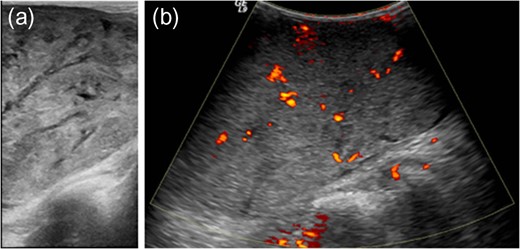

Gray-scale ultrasound shows a circumscribed, solid mass with heterogeneous internal echotextures, including hyperechoic, hypoechoic and multifocal anechoic areas, some of which were linear cleft-like in shape (a) and the color Doppler sonography demonstrates increased intralesional vascularity (b).